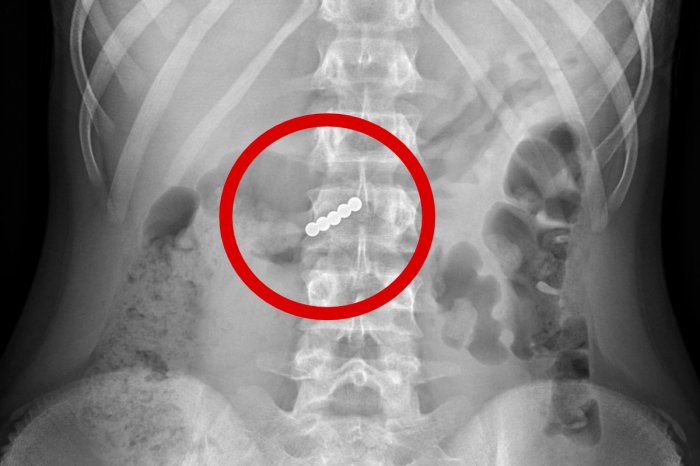

Ako informuje pražská Fakultná nemocnica Motol, prijali a ošetrili päť detí, ktoré sa podľa dostupných informácií inšpirovali výzvou na sociálnej sieti TikTok s názvom „TikTok piercing challenge“.

Deti pomocou guľôčkových magnetov chceli imitovať, že majú piercing napríklad v jazyku. Podľa nemocnice ale následne vo všetkých prípadoch došlo k nechcenému prehltnutiu magnetov.

„Pri prehltnutí viacerých magnetov alebo magnetu a kovového predmetu hrozí ich spojenie, ktoré môže k sebe pritiahnuť napr. žalúdok a črevo a spôsobiť jeho poškodenie alebo aj dokonca prederavenie (perforáciu), zápal a v niektorých prípadoch aj ohrozenie života,“ uvádza FN Motol.